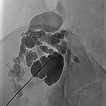

Additional puncture approximately 5 cm cranially into another cystic compartment of the lymphatic malformation. This compartment does not communicate with the lower part of the malformation still visible caudally. Therefore, it must be sclerosed separately in order to successfully occlude the entire lymphatic malformation.

New sclerotherapy in a second session using direct puncture technique under ultrasound guidance into the remaining cystic areas of the lymphatic malformation (X-ray overview image after contrast injection via the needle). After injection of the contrast medium, the punctured area is then evacuated of fluid as completely as possible. Then the sclerosing agent, here picibanil (OK-432), is injected via the same needle position.